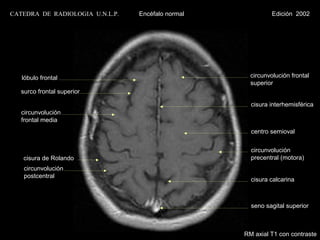

CATEDRA DE RADIOLOGIA U.N.L.P.   Encéfalo normal             Edición 2002

lóbulo frontal                                    circunvolución frontal

superior

surco frontal superior

cisura interhemisférica

circunvolución

frontal media

centro semioval

cisura de Rolando                                 precentral (motora)

postcentral

cisura calcarina

seno sagital superior

RM axial T1 con contraste